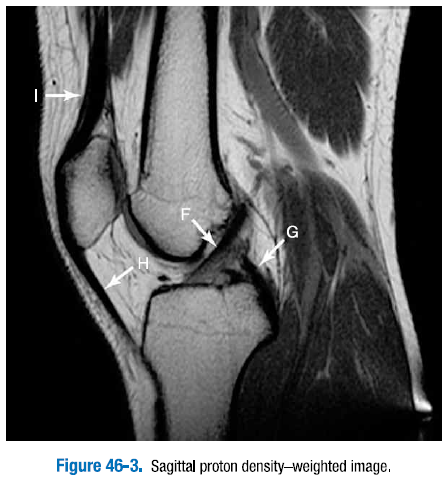

3. 그림 46-1 ~ 그림 46.4에 있는 무릎의 표지된 정상 구조물을 확인하라.

A. 전방십자인대   B. 후방십자인대   C. 내측측부인대

D. 내측 슬개골지대   E. 내측광근

F. 전방십자인대   G. 후방십자인대   H. 슬개골건   I. 대퇴사두근건

J. 외측반월판 전방각   K. 외측반월판 후방각   L. 슬와근건